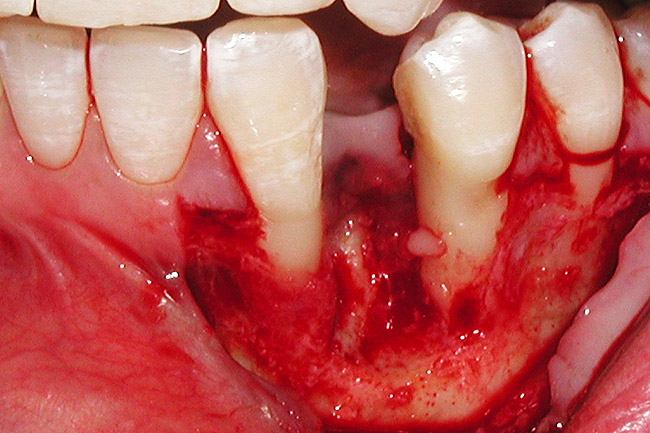

Figure 4  Vertical ridge defect in site No. 22.

Figure 4

Figure 5  Horizontal ridge defect in site No. 22.

Figure 5

The patient had no medical concerns and had a history of an implant placement in December 2002 when she was 25 years old. In February 2005, she presented with a mobile implant and an associated advanced peri-implantitis. Radiographic review at the initial examination demonstrated significant destruction of the dentoalveolar ridge around the implant as well as around the adjacent natural dentition. Emergency-based treatment involved surgical implant removal only and debridement of the infection (Figure 4 and Figure 5). Following uneventful healing, an advanced ridge defect was apparent at the edentulous site and moderate and advanced attachment loss noted at No. 22D and No. 21M, respectively (Figure 6 and Figure 7). This case demonstrates bone loss of two separate origins: lack of bone because of tooth agenesis and destruction of bone from inflammatory peri-implantitis.